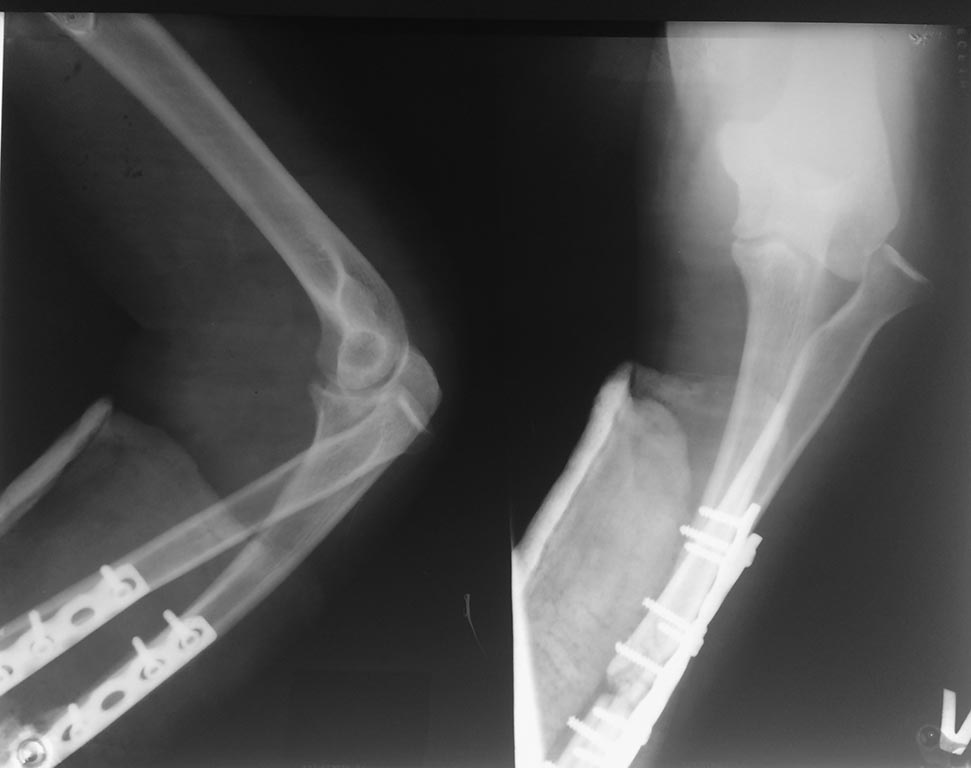

Предлагаю обсудить варианты оперативного лечения последствий тяжелой

травмы предпоечья.

Молодая пациентка. Травма несколько месяцев назад. Рука попала в

тестомешалку. Открытый questilio 3. Перелом костей предплечь, открытый

вывих в лучезапястном суставе. Дежурной бригадой сделано пхо, синтез

костей предплечья. Все зажило, хотя не совмем гладко. А на контроле -

вывих головки луча. Соотношение в дистальном лучелоктевом суставе

правильное. Вопросы по объему операции:

1 . Тупо резекция головки?

2. Укоротить лучевую проксимально , вправить вывих и синтез?( вопрос

только по n. radialis) . Кто нибудь так делал?

3 . Пересинтезировать локтевую и восстановить ее длину, вправить

головку. ( есть риск инфекции)

Понятно, что выкинуть головку проще всего. Как насчет двух последних

вариантов.